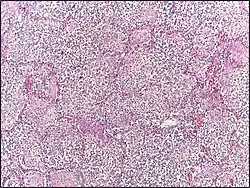

![]() | Follicular lymphoma | Micrograph showing a small B-cell lymphoma compatible with follicular lymphoma. H&E stain. | Category: Histopathology of follicular lymphoma | Follicular lymphoma |